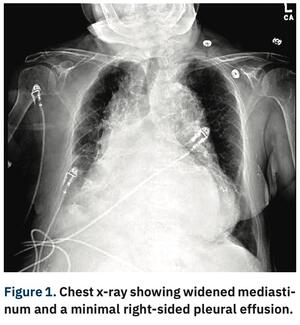

Thoracoabdominal aortic aneurysms (TAAA) result from continuous dilation of the descending thoracic aorta extending into the abdominal aorta. Degradation of the structural proteins that form the medial layer of the aorta, like collagen and...